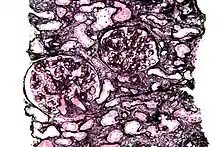

Micrograph of a kidney biopsy stained with a Jones stain.

It stains for basement membrane and is widely used in the investigation of medical kidney diseases.

The Jones stain demonstrates the spiked GBM, caused by subepithelial deposits, seen in membranous nephropathy.